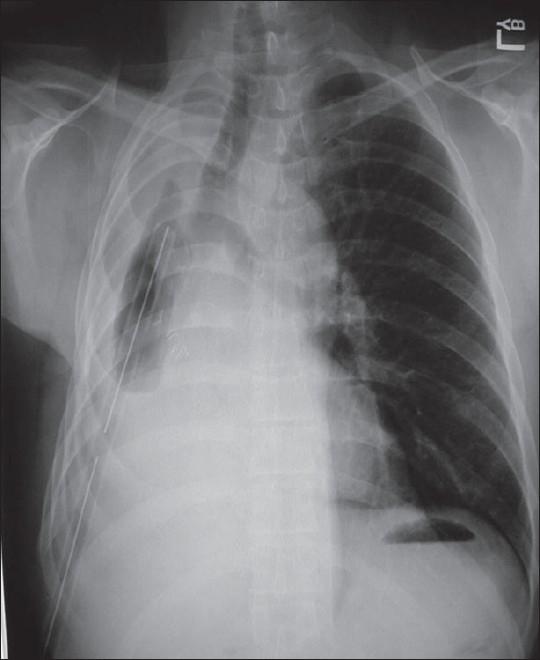

Thoracoscopic management of empyema thoracis.

Appropriate management of empyema thoracis is dependent upon a secure diagnosis of the etiology of empyema and the phase of development. Minimal access surgery using video-assisted thoracoscopy (VATS) is one of many useful techniques in treating empyema. Complex empyema requires adjunctive treatment in addition to VATS.

脓胸的恰当管理取决于对脓胸病因及发展阶段的准确诊断。使用电视辅助胸腔镜(VATS)的微创手术是治疗脓胸的众多有效技术之一。复杂脓胸除了VATS外还需要辅助治疗。